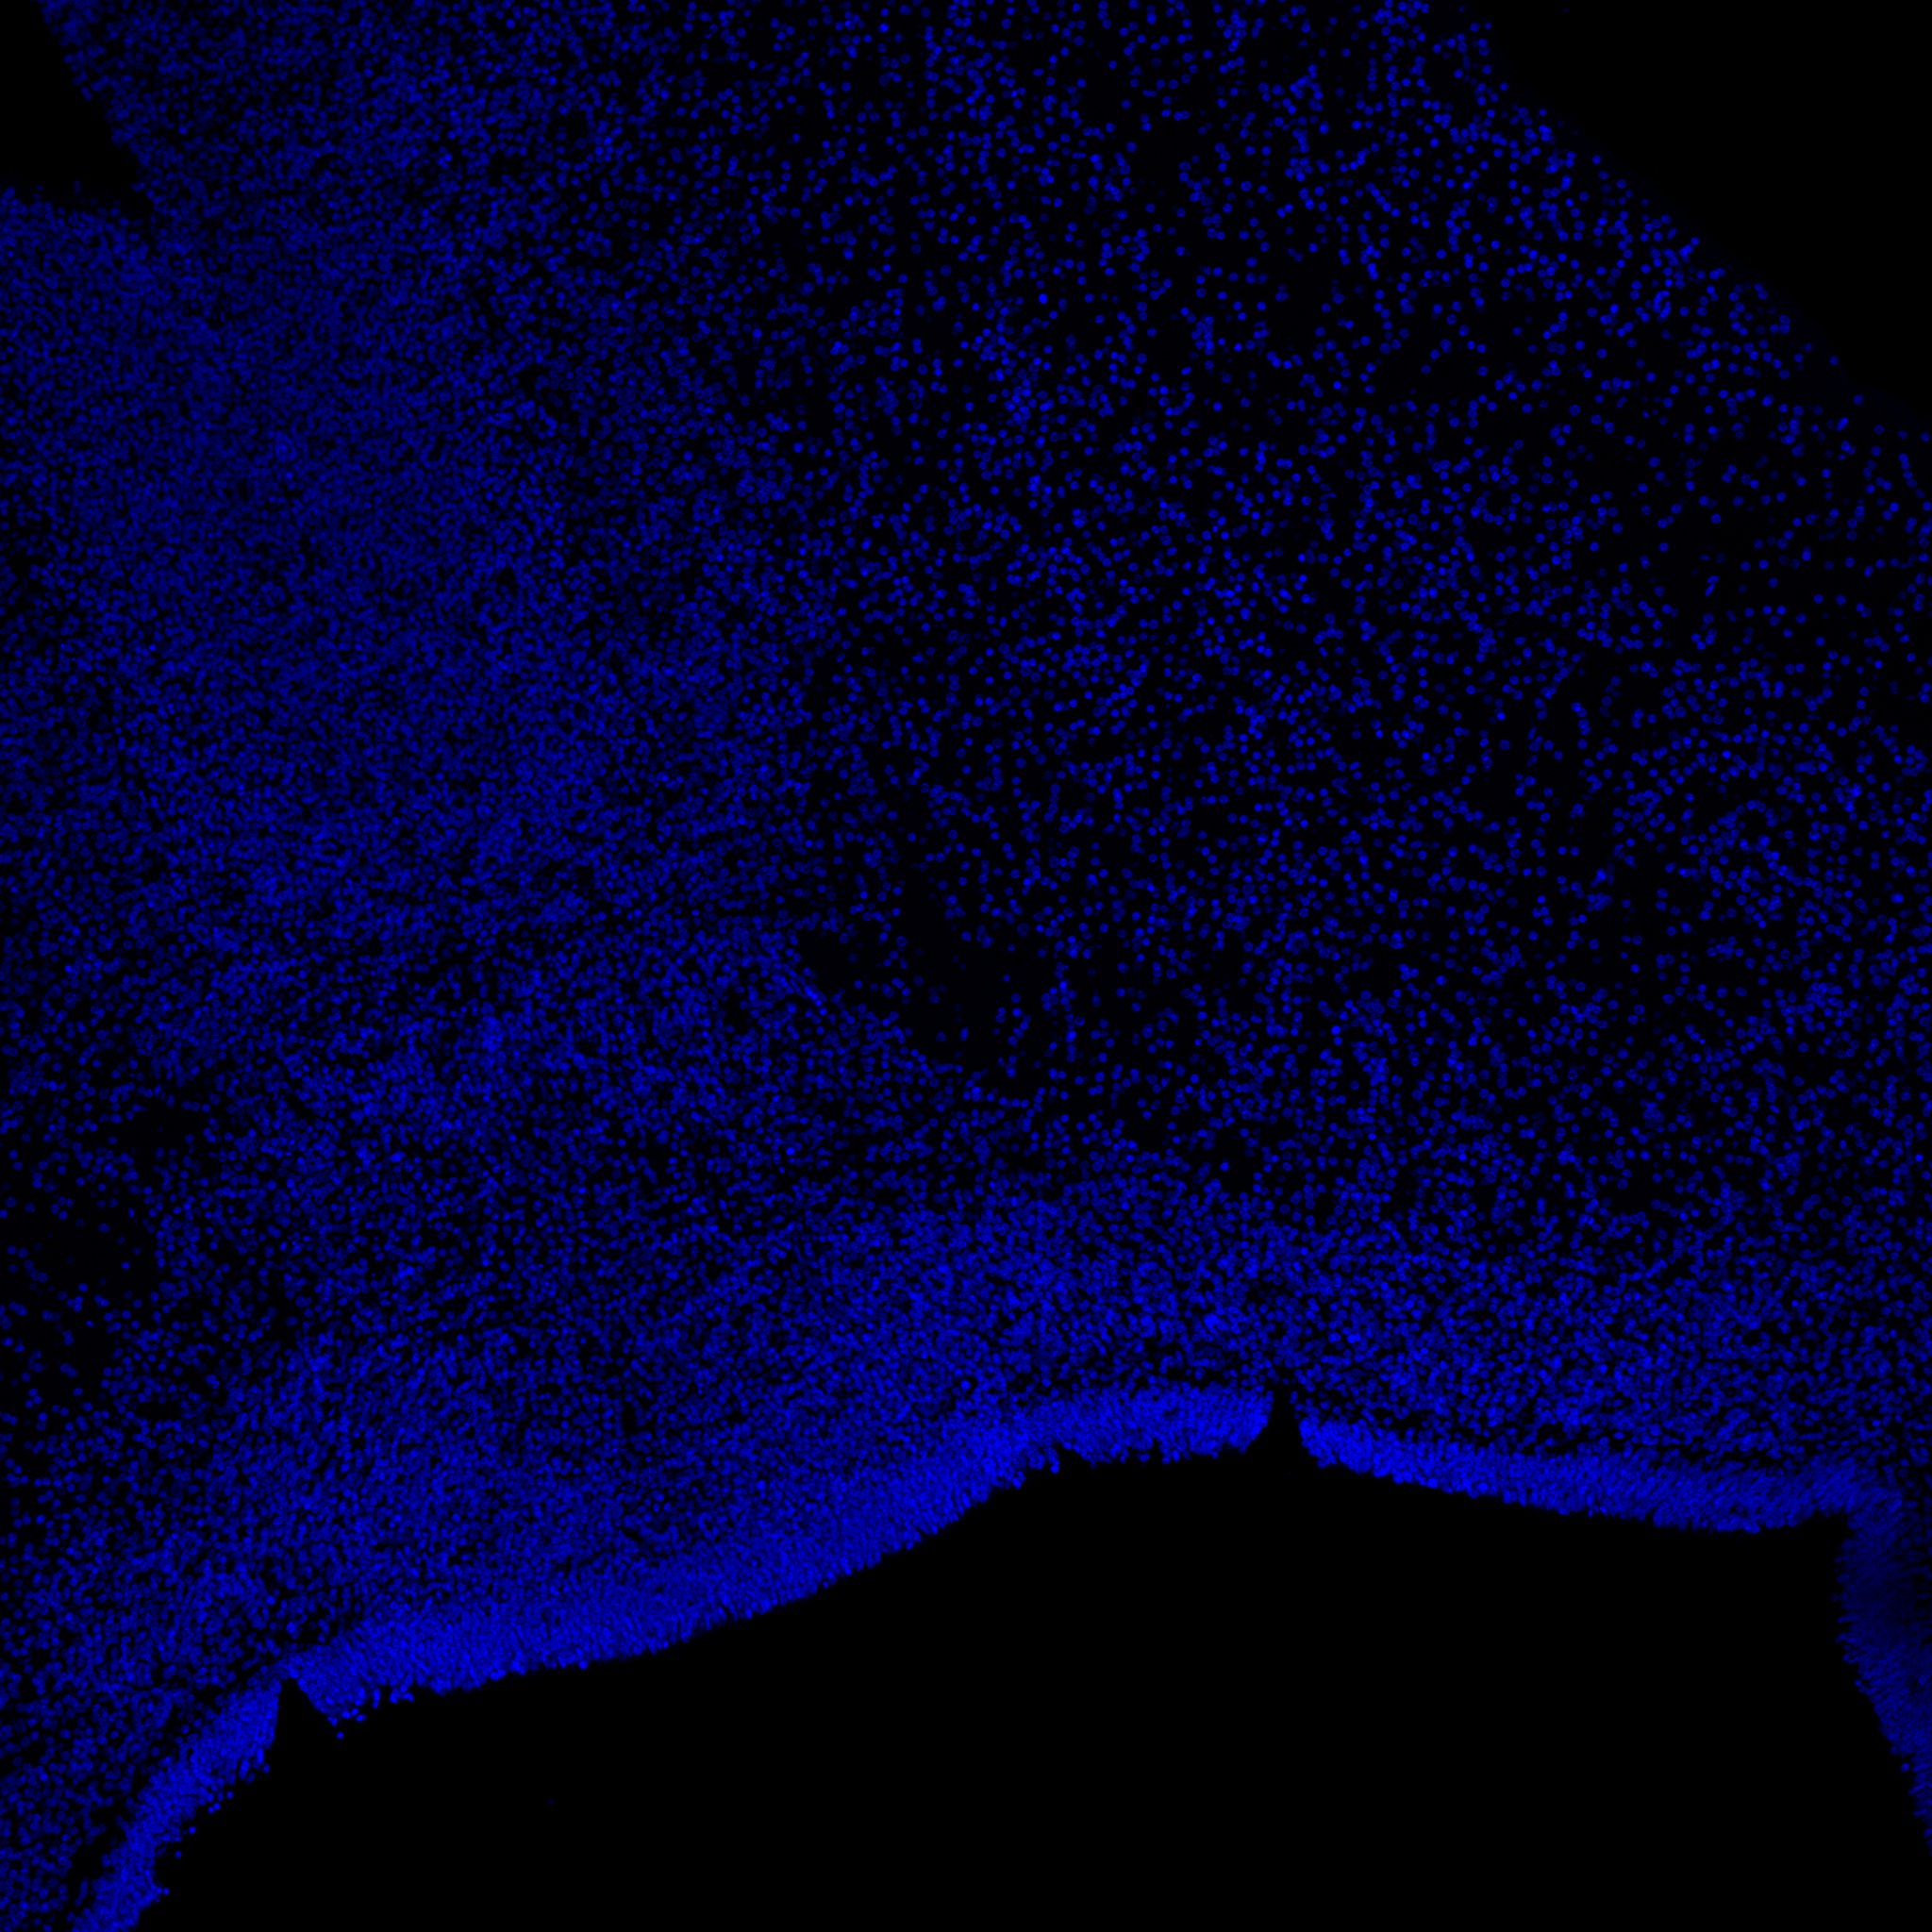

DAPI

6PCW human midbrain

7PCW human midbrain

11PCW human midbrain

13PCW human midbrain

22PCW human midbrain